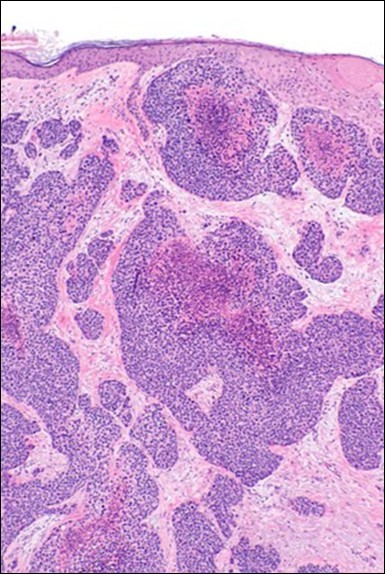

Granular arrangement of malignant cells and intercellular bridges are conspicuous with the demonstration of nuclear atypia, pleomorphism, prominent mitosis and tumour necrosis. A peripheral palisade is discernible within the cellular aggregates. Mitotic figures are common and can be quantified as up to 12 mitosis/ high power field. Tumour differentiation can prominently be of the ductal category with the demonstration of intra-cytoplasmic lumina. Comedo type tumour necrosis is evident along with foci of squamous differentiation The neoplasm is reactive to periodic acid Schiff ‘s (PAS) stain. (Figure 1, Figure 2, Figure 3, Figure 4, Figure 5, Figure 6, Figure 7, Figure 8, Figure 9, Figure 10, Figure 11, Figure 12, Figure 13.

Figure 3.Cohesive accumulations with numerous ductular articulations of carcinoma cells in eccrine porocarcinoma (15).